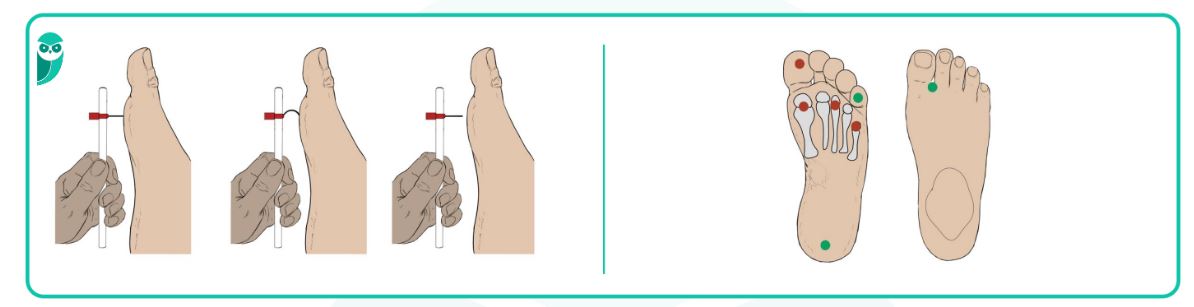

- Passo 5: Teste com o cotovelo (se não tiver termômetro) -Se não tiver um termômetro, use o cotovelo ou a palma da mão. Essas áreas têm a sensibilidade mais preservada que os pés. A água deve estar morna, confortável, nunca quente.

Como Testar a Temperatura sem Termômetro: Métodos Alternativos

Se você ainda não tem um termômetro, não se desespere. O cotovelo ou a palma da mão são métodos seguros para verificar a temperatura da água. A pele nessas regiões tem a sensibilidade mais preservada. Mas vamos combinar: um termômetro de banho é a garantia que você precisa para a sua segurança, ok?

Sim, é um método seguro e recomendado por profissionais de saúde, pois a pele do cotovelo é mais sensível ao calor do que a dos pés com neuropatia.

A chave está na técnica correta: mergulhe a parte interna do cotovelo na água por 5 a 10 segundos. Se a sensação for de morno agradável, está seguro. Qualquer calor mais intenso significa ‘perigo’.